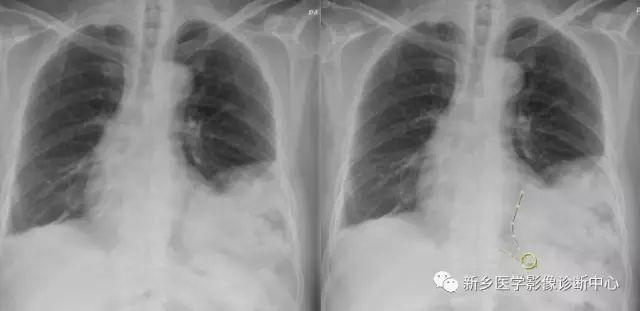

性别:男,年龄:88岁,咳嗽数月余

A、食管裂下端憩室

B、食管静脉曲张

C、食管癌

D、食管裂孔疝

正确答案是:D、食管裂孔疝;

[影像描述]

CT:贲门级部分胃体组织通过食管裂孔进入胸腔内,位于膈上,其上段食管明显扩张。